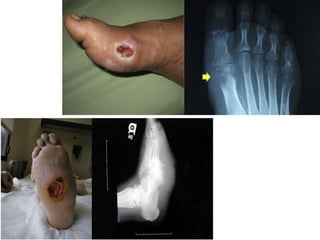

Using herbal treatment

Self treatment

Afraid from amputation = amputation